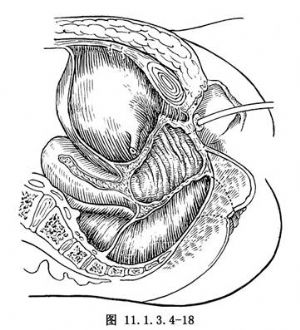

術後尿道固定於恥骨後骨膜上,膀胱前壁固定於腹直肌後面,消失了的尿道后角得以恢復(圖11.1.3.4-18)。